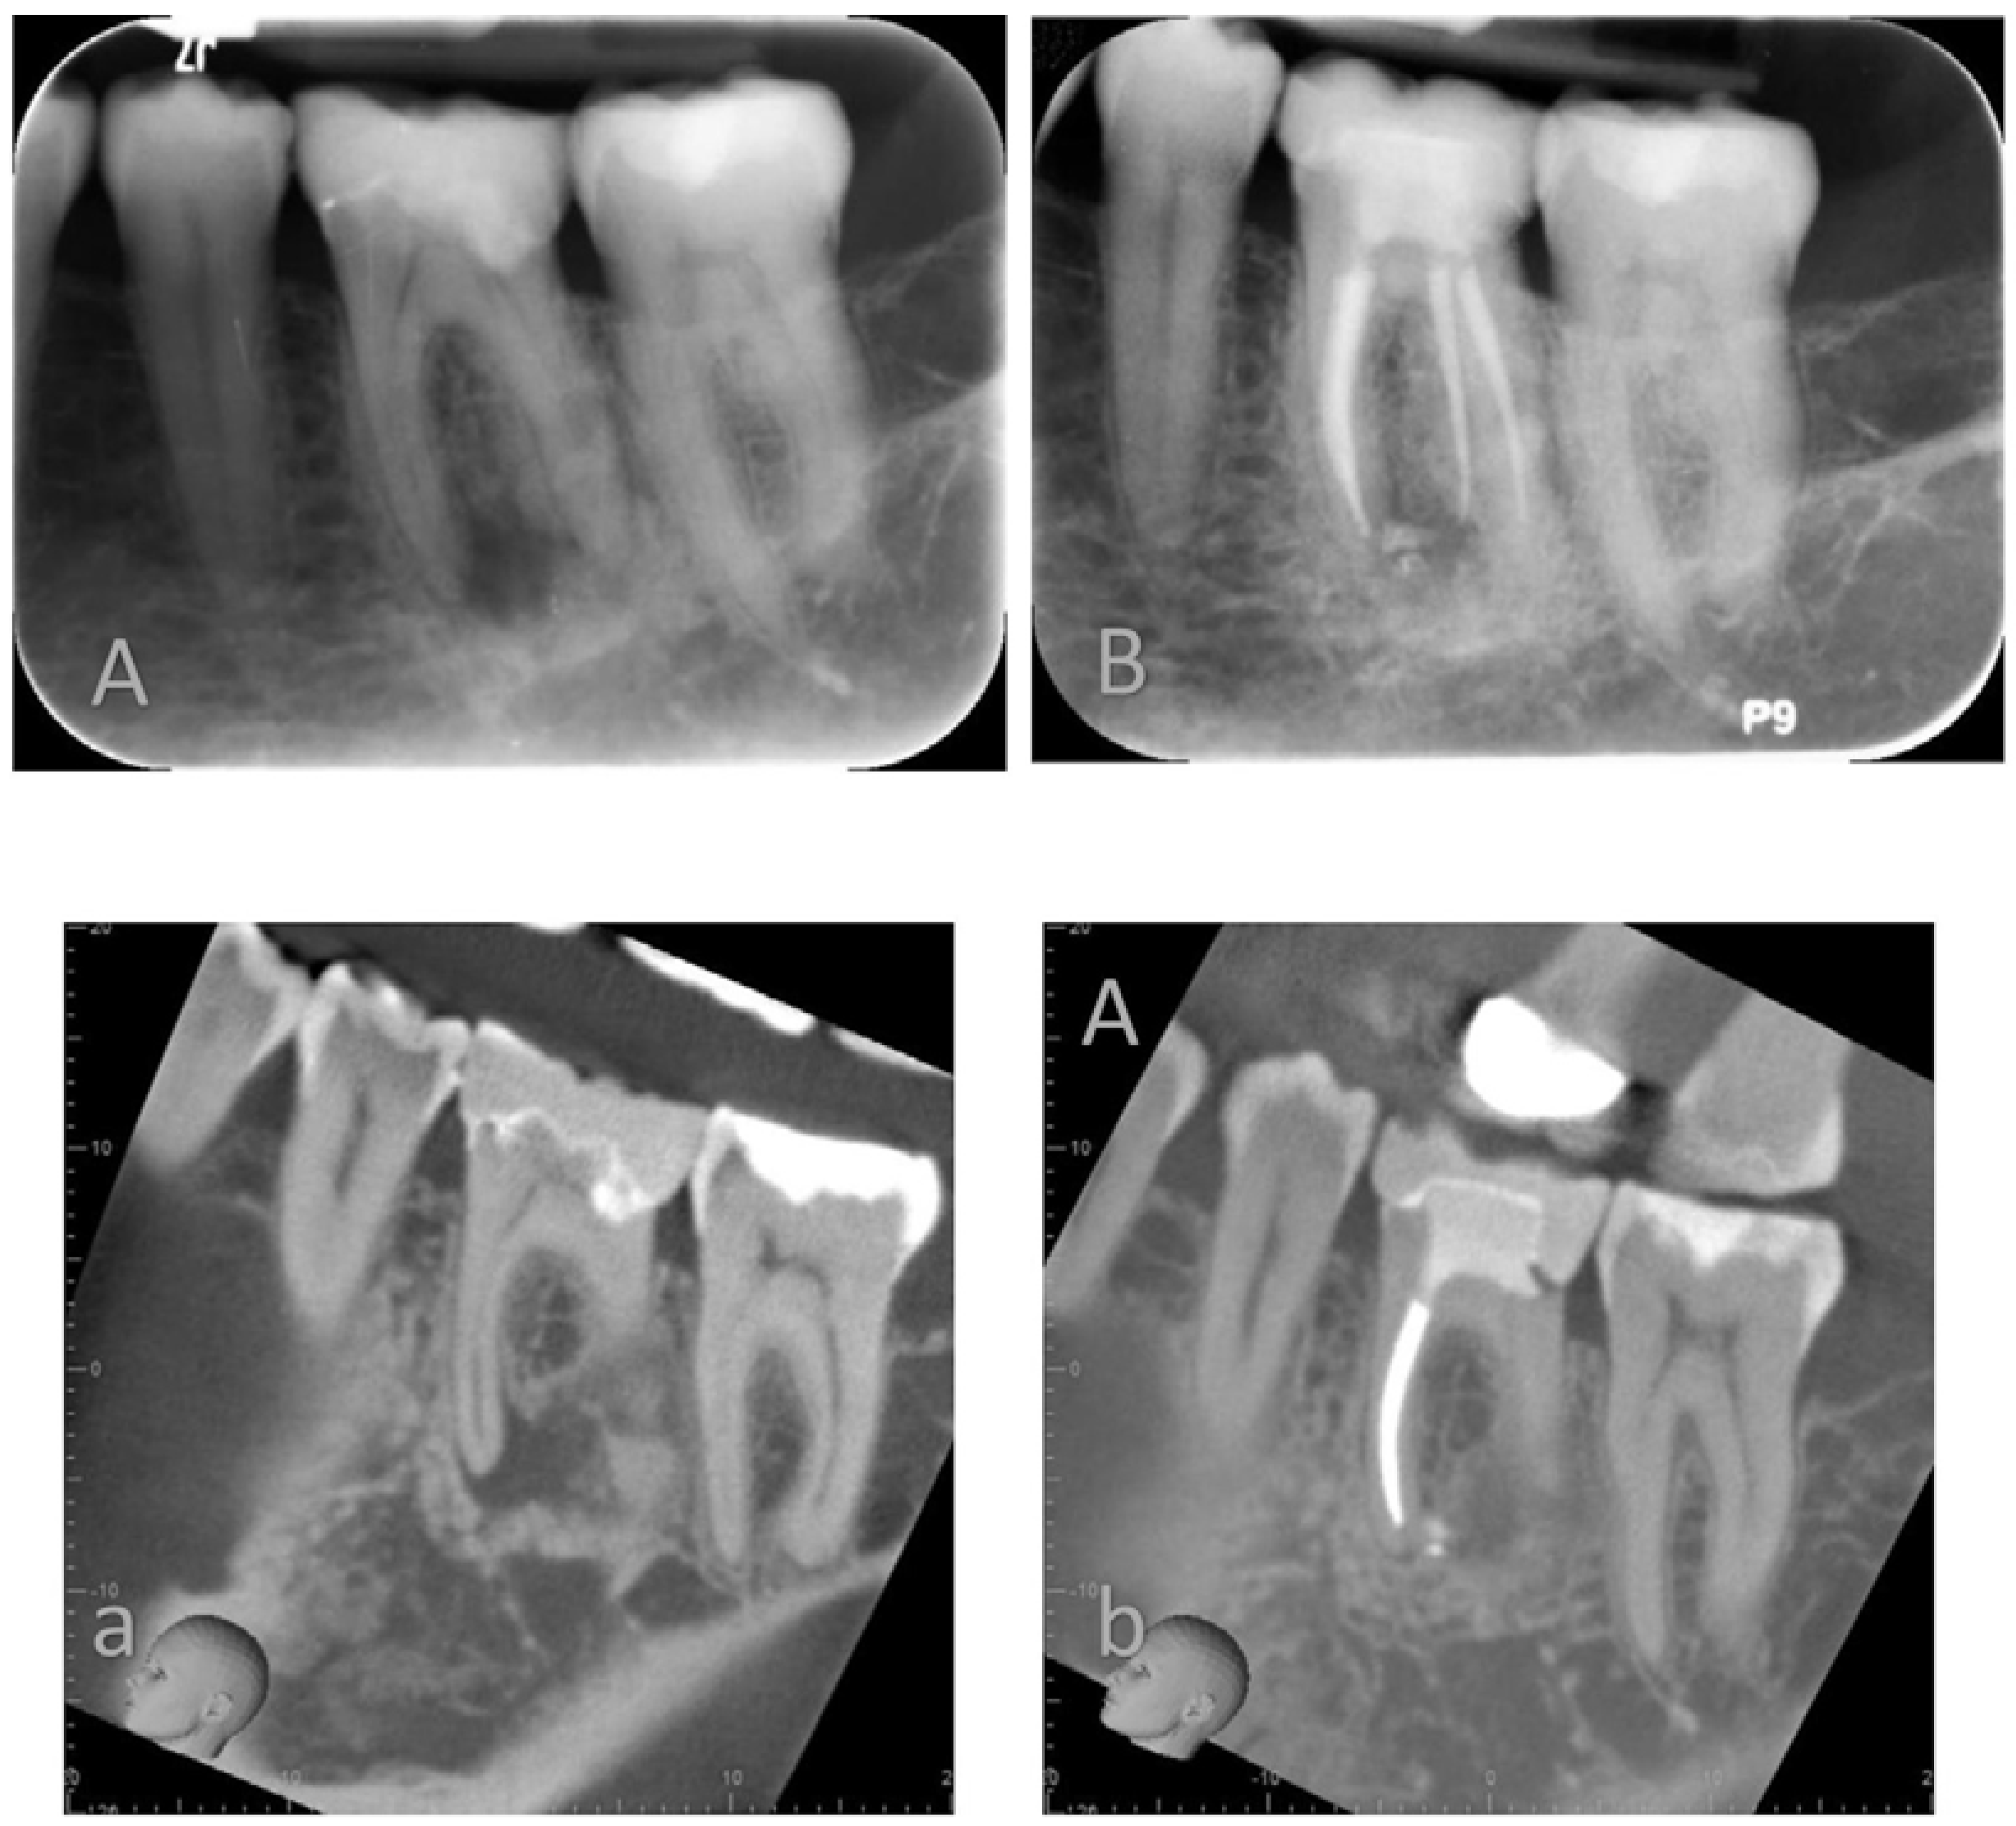

In this non-randomized clinical trial, the clinical outcome of two different root canal obturation techniques was compared with CBCT imaging at one-year follow (Figure 2 and Figure 3). The patient population was enrolled and treated in a teaching hospital by senior postgraduate trainees under specialists’ supervision.

Figure 2. Lower left mandibular first molar root filled using a warm vertical condensation technique and AH plus root canal sealer. Preoperative Periapical X-ray (A) and Cone Beam Computer Tomography (a) and recall PA X-ray (B) and CBCT (b) at 12 months.